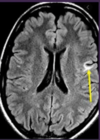

DX?

Infarto cerebral debido a ACM izq